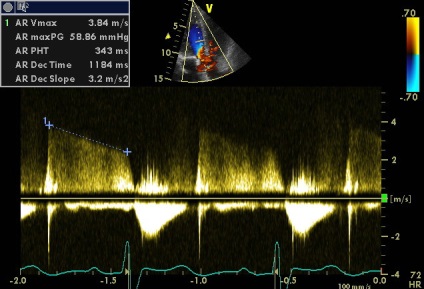

Sinus Valsalva - egy zseb-szerű szerkezet határolt szálas gyűrűt szelepcsappantyú, és az illető semiiunaris aorta fal, annak felső határa - sino-csöves csatlakozás. A falakat a két szinusz van a szája, a jobb és a bal koroanrnyh artériák, és hívják a jobb és a bal koszorúér sinus, és a maradék egyharmad - a nem koszorúér. A beteg egy diszkontinuitás az aneurizma a jobb coronaria sinus Valsalva (ünnepelte gyakrabban), mint látható parastrenalnyh szakaszok rövid és hosszú távú (egy lejtőn) tengelyeken. Számos egyéb, kevésbé gyakori aneurizma orrmelléküregek, még kevésbé egyidejűleg 2 vagy 3 (nem tévesztendő össze egy egyszerű kiterjesztése aortagyök szintjén az orrmelléküregek, ellentétben, amelyek továbbra is legyen tarsoly alakú kiemelkedés a fal, mint a mi beteg). A formáció egy ilyen aneurizma egy patológiás állapottal vegyületet struktúrák bázis szelep szórólapok és aorta fal. Fistulák (kóros anasztomózis) a szinuszok szintet, és anélkül, aneurizma (pl, amely különféle fertőző endocarditis). Csakúgy, mint az aneurizma nem bonyolítja egy hosszú szünet (és általában nem, hogy klinikailag). A rés a kialakulását a sipoly kiváltható trauma, szívbelhártya-gyulladás, magas vérnyomás, stb de néha spontán. A szünet alakul súlyos volumen túlterhelés, olyan funkciókkal, hemodinamikus megnyilvánulások, attól függően, hogy melyik kamrában visszaáll az aortából. Ebben az esetben, a reset határozzuk meg a jobb kamrai kiáramlási traktus (2. típusú), egy jelentős növekedést véráramlást a bal kamrai kiáramlási traktus (disztálisan a sipoly, miközben a szisztémás keringésbe csökken). Drámaian megnövekedett a nyomás a jobb kamra (amint azt a gradiens tricuspidalis regurgitáció + jelei megnövekedett nyomás a jobb pitvarban). De pulmonális sávval egy reflexszerűen hipovolémia, amíg részlegesen „védett” (görcs) az ilyen akut volumen túlterhelés (fokozott jelei rezisztencia lehet számítani). A helyzet sürgető, és előírja szívsebészet.

Tachycardia idején szkennelés nem (a klip jobb alsó sarkában a csatorna EKG monitorozás szívritmus alakzatnak, akkor változik a 73-77 perc). De érszűkület (akár minimális) szintén nem (igazad van), és enyhe növekedés sebessége és a színátmenet összefüggésbe hozható a megnövekedett perctérfogat (verőtérfogat LV). „Körülbelül egyenlő a VTI” csak beszélni a közelítő egyenlőség a terület és a terület AK BT LV (aorta regurgitatio nem számít, mert még kicsi, annak ellenére, hogy az alacsony PHT. Ebben az esetben a gyorsított összehangolás LZH- Ao nyomás nem jár gyors növekedése a diasztolés nyomás a bal kamrában, mint a súlyos aorta regurgitáció, és a gyors nyomás csökkenése az aortában miatt ürítőnyílás a sipoly).